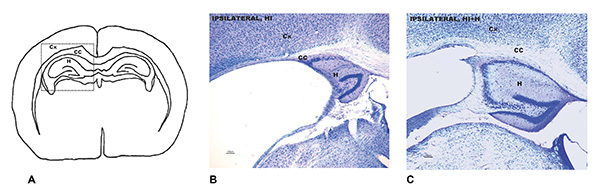

A: Brain area affected by hypoxic and ischemic injury. B: Neuropathological analysis demonstrating brain damage in adult mice that as newborns suffered hypoxic and ischemic injuries and did not received sensory stimulation. C: Neuropathological analysis on the same area in adult mice that were stimulated.

The results revealed that this intervention had a notable neurological protection on both genders throughout their lives, but researchers highlight that the effects were especially positive among males. The histopathological analysis in males demonstrated 50% less brain damage compared to the non-stimulated mice. There was a 30% decrease among female mice. The neurological protection in both genders was correlated to the improvement of functional capacities, reflexes, and an improvement in memory results.

In relation to brain areas, the region involved with motor control and learning and memory (caudate/putamen) was the one to register the largest difference in males, with 80% less damage. In females, the main improvement was a 66% reduction in atrophy to the corpus callosum, a nerve tract connecting the left and right brain hemispheres.